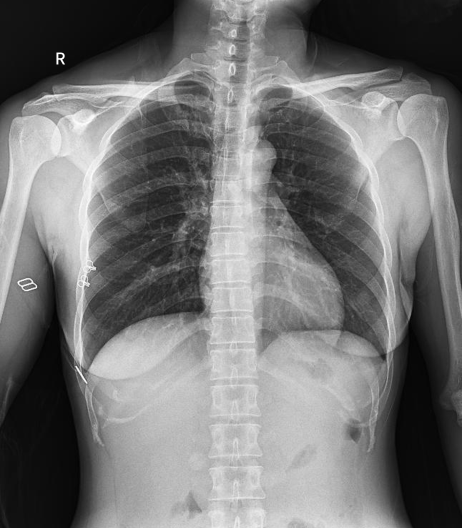

临床图片